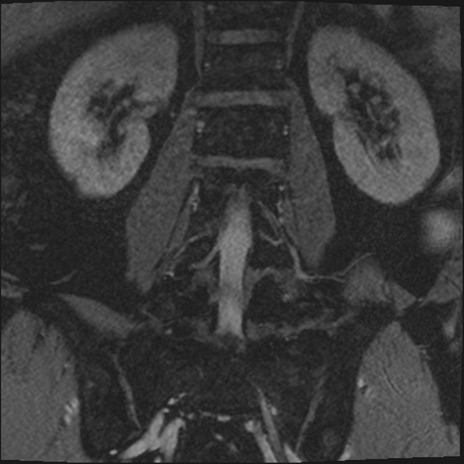

【整形】TIPS症例2 腰椎MRI 3D(冠状断像)

【症例】70歳代男性

【主訴】左下肢痛

【現病歴】2週間前くらいから腰痛、左下肢痛あり。左臀部から大腿、下腿外側のしびれが常時ある。歩行とともに同部位の痛みあり。

【身体所見】Lasegue70-/60+、Bragard-/±、PTR ±/±、ATR -/-、IP 5/5、TA 5/4、TS 5/5、EHL 右第1足趾なし/3、FHL 5/5、hypersthesia(-)、足背動脈触知良好

異常所見と診断は?